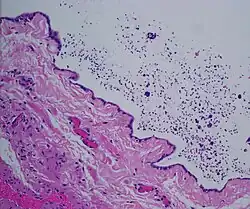

| Spermatocele | |

| Ultrasound of a testicle (grey) and a spermatocele (black). | |